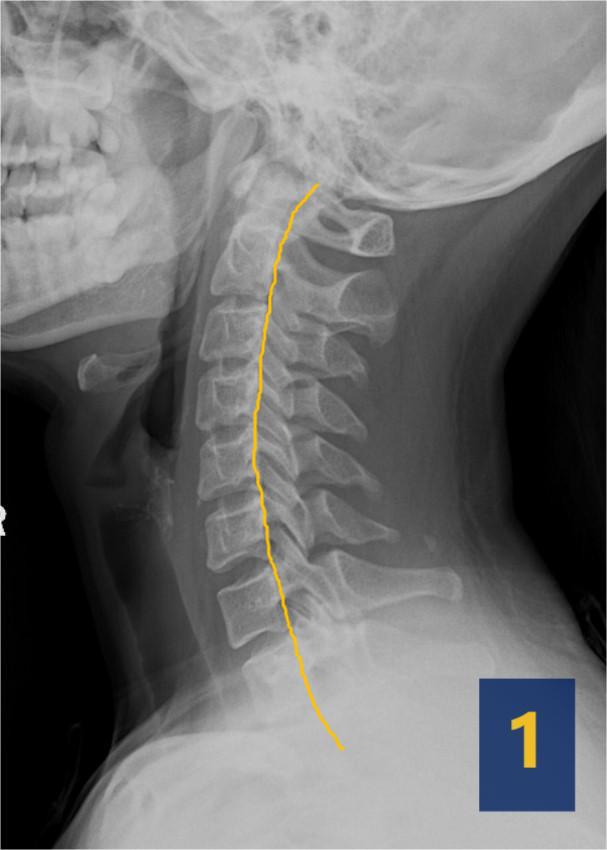

常规颈部侧位片观察颈椎生理曲度的变化:同为40岁左右的颈椎,图1是正常的,图2为异常。

人出生的时候,颈椎曲度是向后凸起的,随着抬头、爬行、坐立、直立、行走,目视前方,身体后侧肌肉韧带等软组织变强拉起身体,颈椎就需要向前凸起。医学上把颈椎向前的弧形凸起称为颈椎生理曲度。颈椎生理曲度能有效增强颈椎的弹性,减缓由重力带来的冲击作用,可最大程度保护大脑和脊髓免遭外界损伤。